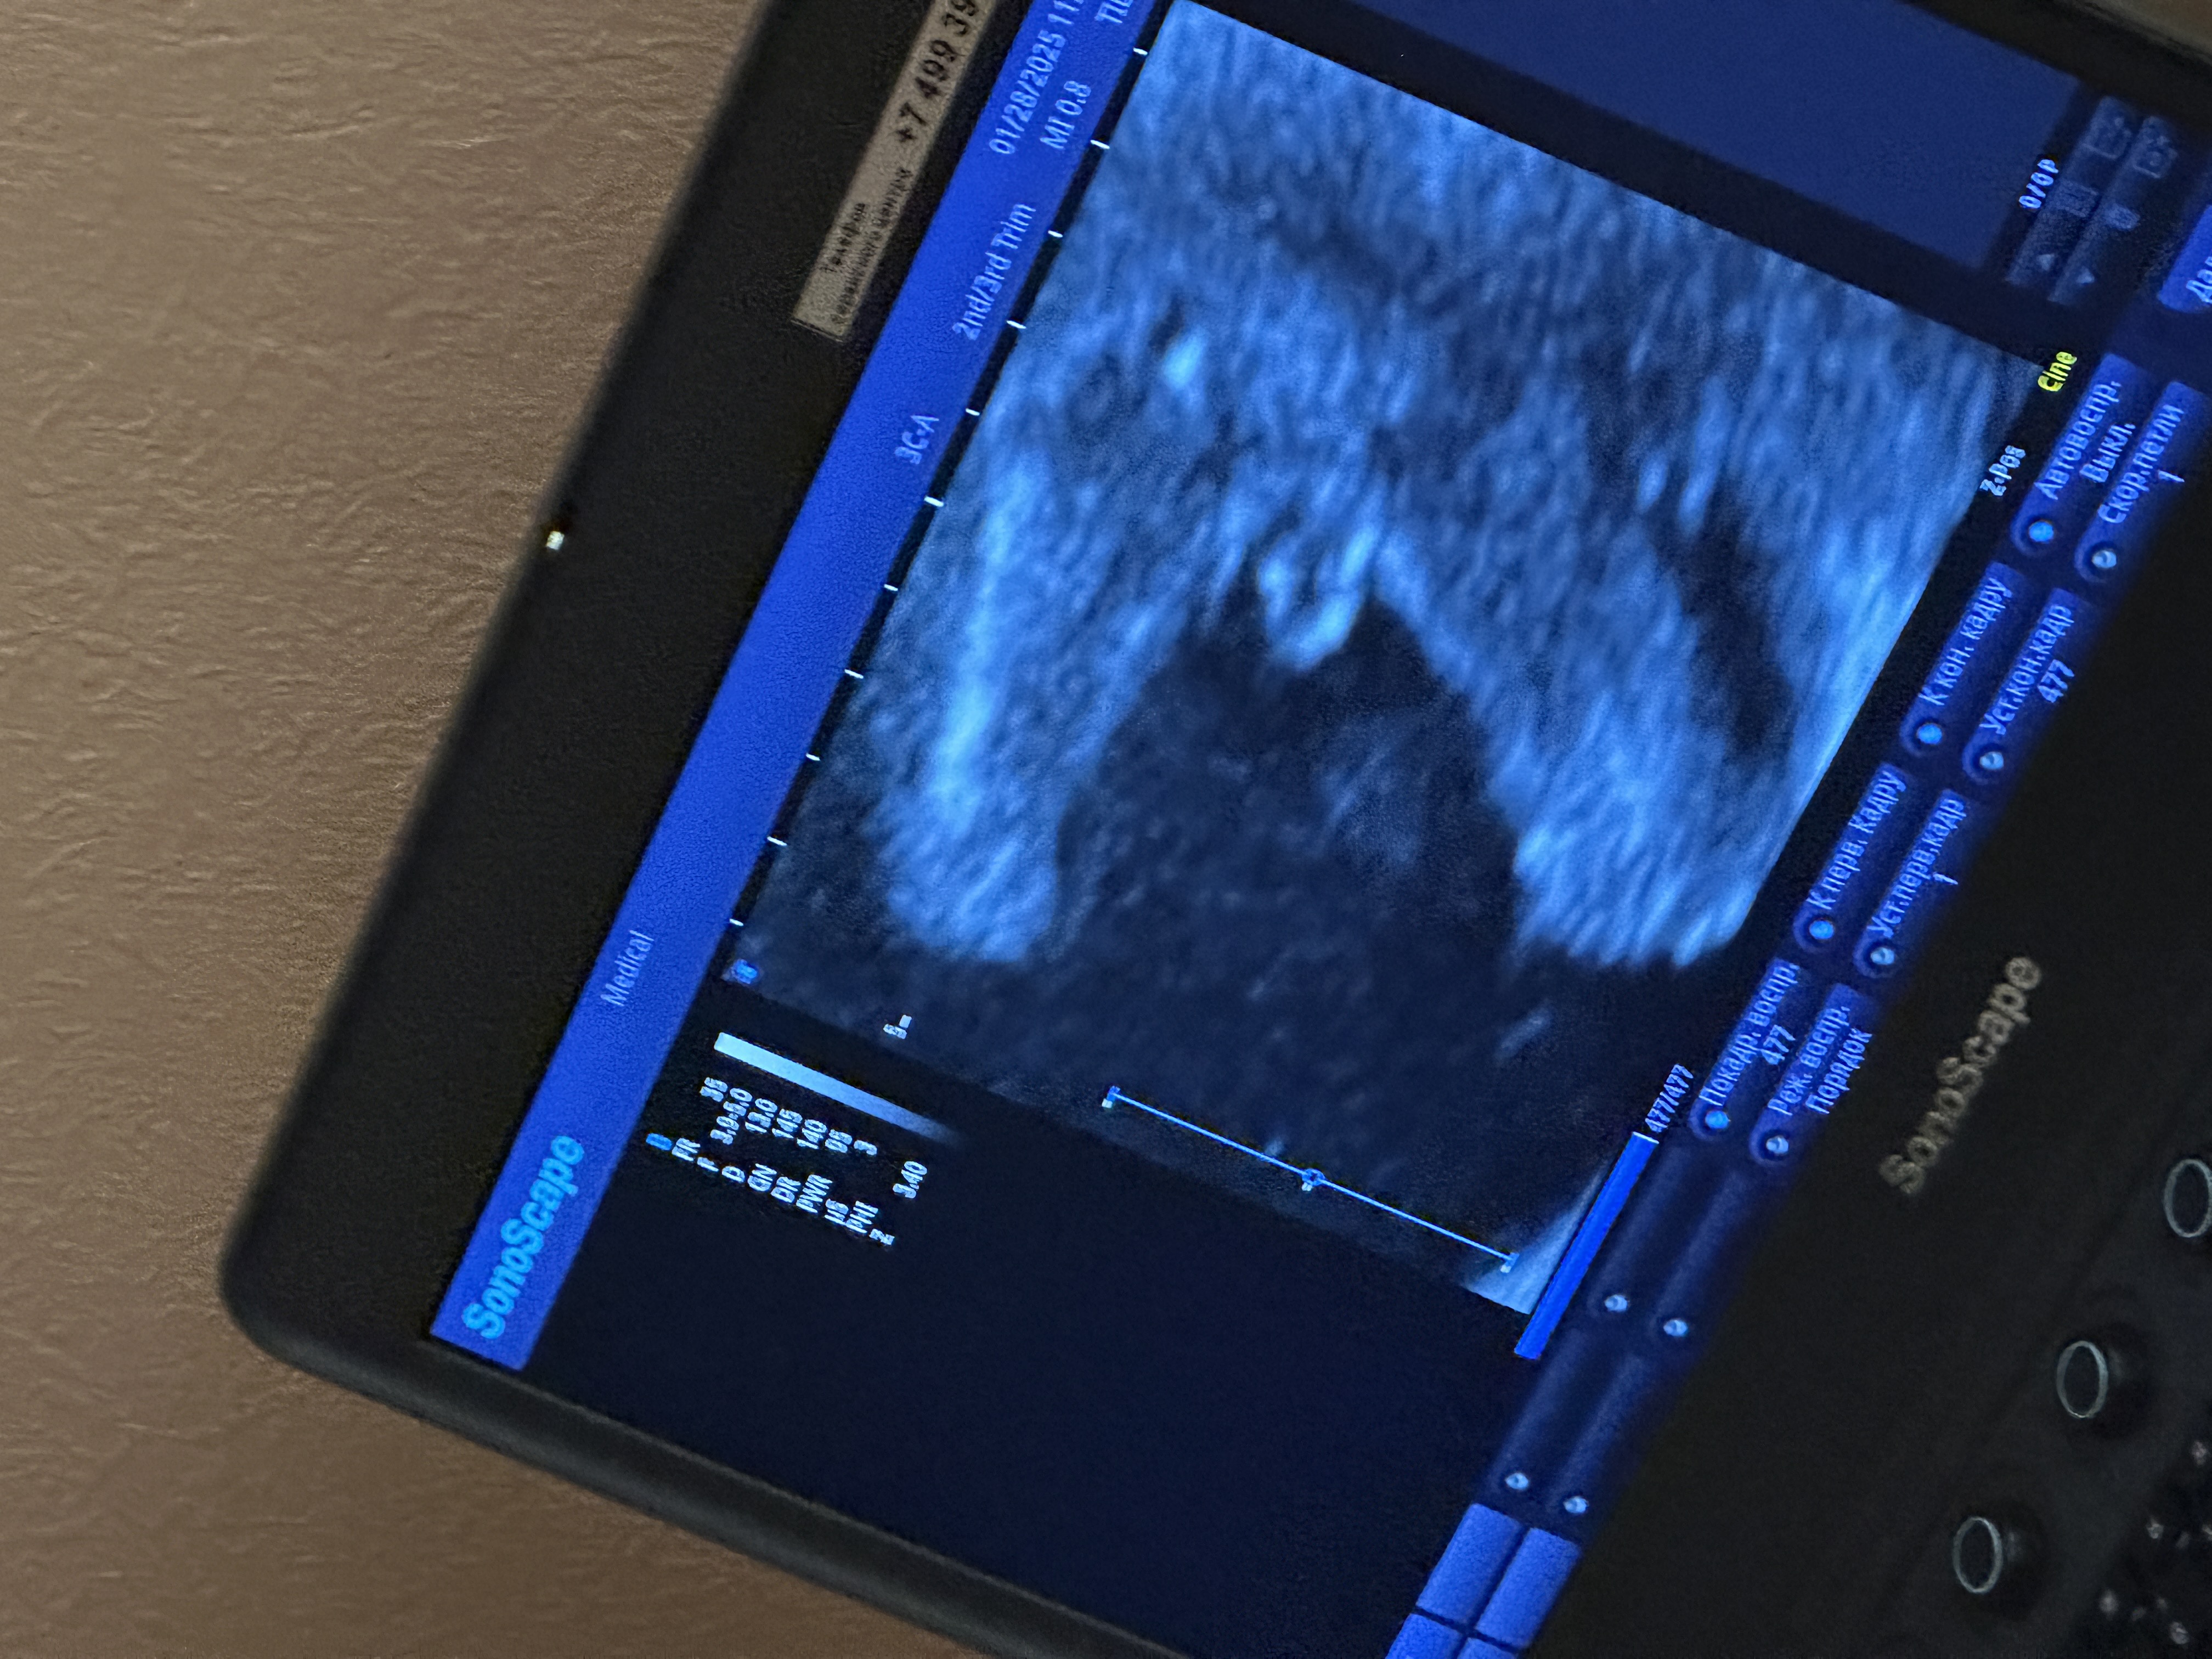

Анастасия в Зачатие 9 месяцев Все же Мальчик? 🤔 УЗИ Посмотрите еще 20 записей на эту тему Отменить Ответить Ксения Панюкова Без сомнений))) 24.02.2025 Ответить Анна У нас такое же фото🥰 24.02.2025 Ответить Алёна Хаустова 1000% парень) 24.02.2025 Ответить Анастасия Мальчик конечно 24.02.2025 Ответить Бусинка Мальчишка 😅 у нас такое же узи было, только на сроке 15,6)) 24.02.2025 Ответить Юлия Конечно, пацан💪🏻 24.02.2025 Ответить Святая инквизиция Срок? 24.02.2025 Ответить Анастасия Karmilla, 17н 24.02.2025 Ответить Святая инквизиция Анастасия , тогда да, мальчик) 24.02.2025 Ответить Мама Стифлера 💯 24.02.2025 Ответить Узи 20 дпо УЗИ Чаты Беременных Выберите чат: Январята-2026 Февралята-2026 Мартята-2026 Апрелята-2026 Майчата-2026 Июнята-2026 Июлята-2026 Августята-2026